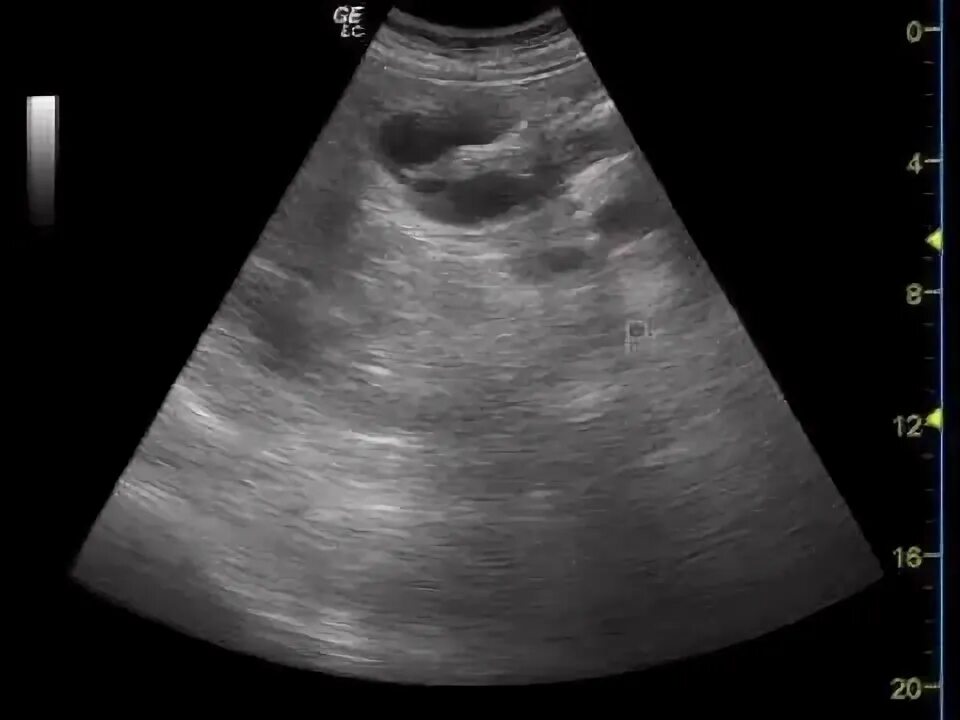

Делают узи желудка или нет